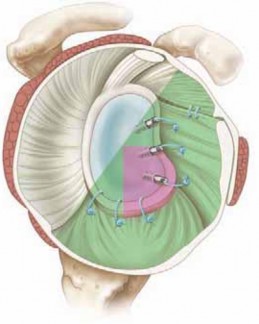

Anchor Placement and Capsulolabral Plication

With the glenoid prepared and the tissue mobilized, fixation begins at the most inferior aspect of the lesion, typically at the 5:30 or 6 o'clock position. Modern fixation relies on either biocomposite or all-suture anchors, typically 1.5 mm to 2.9 mm in diameter. The drill guide is introduced through the anteroinferior portal, and the anchor is deployed on the articular margin (1-2 mm onto the articular cartilage face) to recreate the anatomical labral bumper. The trajectory of the drill is paramount; it must be directed slightly medially to avoid penetrating the articular surface of the glenoid vault.